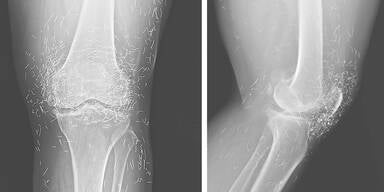

Röntgenaufnahme eines Knies mit auffälligen Fremdkörpern im Gewebe – Ärzte fanden Hunderte winzige Goldfäden.

© New England Journal of Medicine

Die Ärzte stellten nicht nur die typischen Anzeichen einer fortgeschrittenen Arthrose fest – also knöcherne Verdickungen und Verhärtungen –, sondern auch mehrere hundert winzige Goldfäden im Gewebe rund um das Knie. Die Fachleute warnten, dass diese Methode nicht nur ohne nachgewiesenen Nutzen sei, sondern auch gefährlich sein könne.